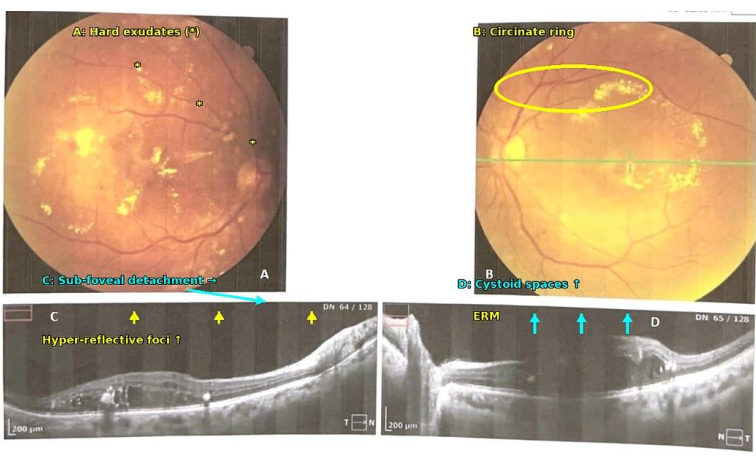

光学相干断层扫描(OCT)显示,高GV伴严重维生素D缺乏患者多见视网膜黄斑水肿、膜性增厚及渗出等病理改变,进一步支持了代谢双重压力与晚期视网膜病变的联系。